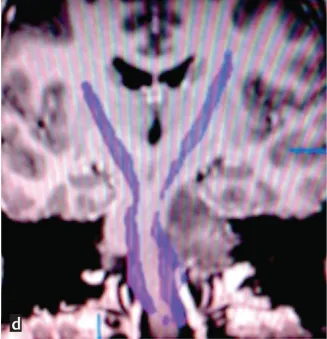

图d:术前扩散张量成像显示脑干肿瘤占位,压迫皮质嵴髓束移位